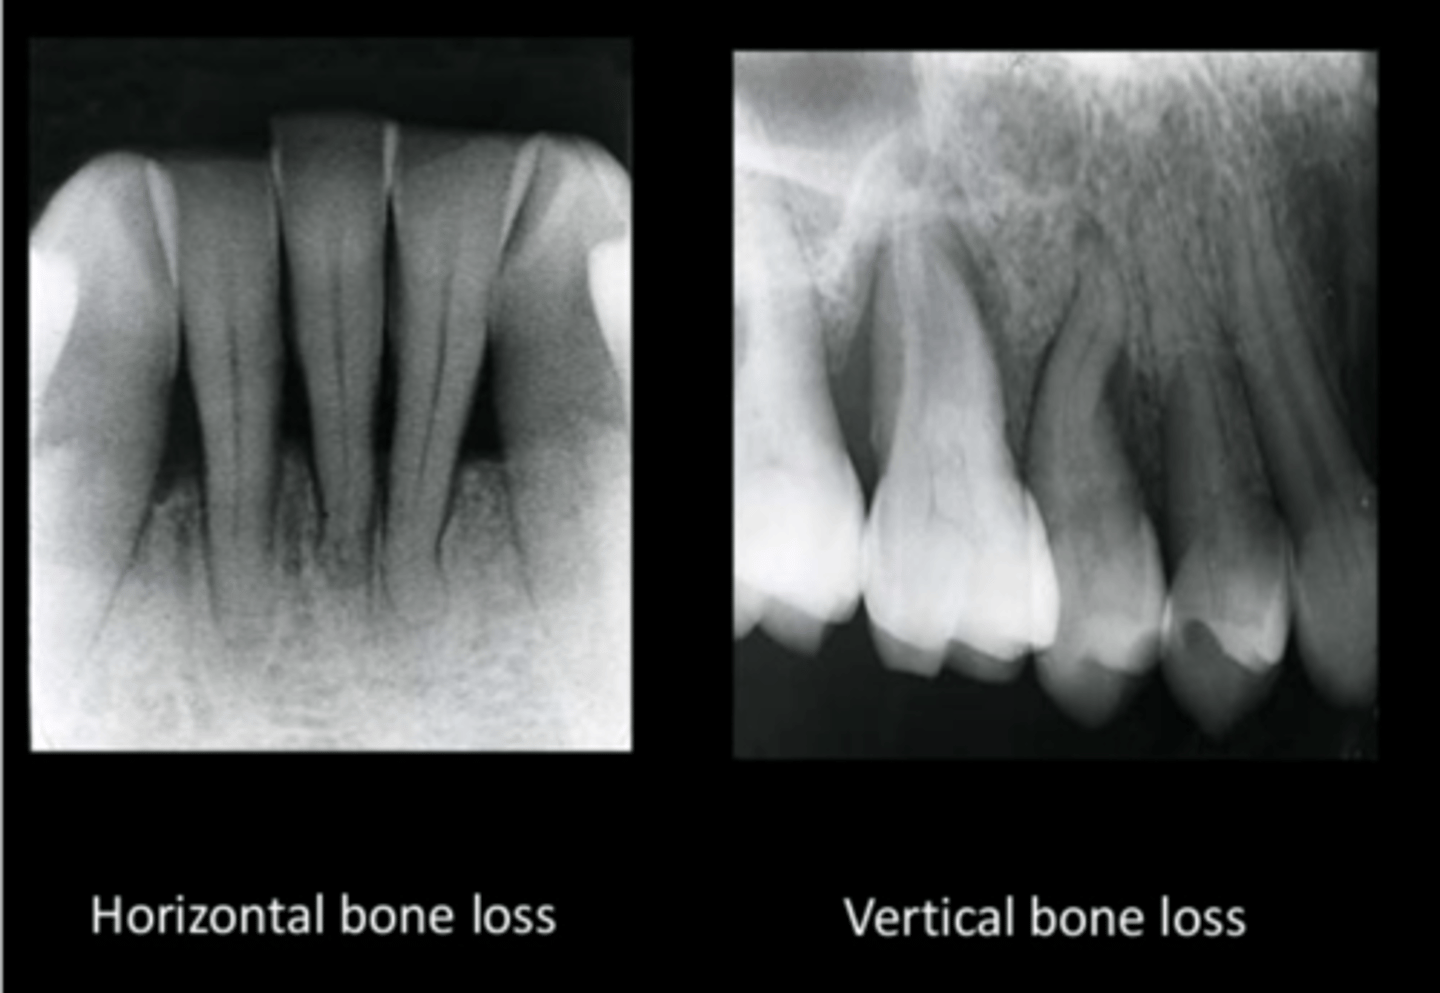

Describe bone loss

<p>Initial bone changes shows crest of bone as fuzzy, not a definite shape</p><p>vertical bone loss</p><p>horizontal bone loss</p>